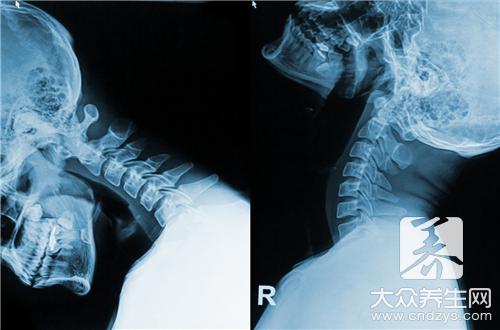

颈椎病现在并不是老年人的专利,越来越多的年轻人也患上了颈椎病,这是怎么回事呢?下面我们跟随小编来了解一下。

年轻人也会患颈椎病吗?

年轻人也会罹患颈椎病,不良的生活工作习惯是年轻人患上这种“中老年疾病”的根本原因。